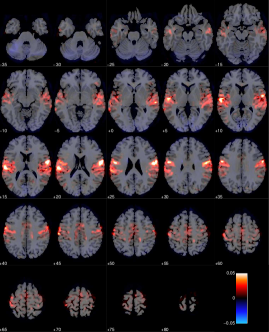

We construct a -nearest neighbor graph using the nonlinear affinity . Figure 14 shows the 4 leading non-trivial global eigenvectors projected onto a sliced brain. Note that the first slice (top left) in such an image corresponds to the bottom of the brain, whereas the last slice (bottom right) corresponds to the top of the brain. The non-trivial global eigenvectors aim to span the most dominant sources of variation in the data, which in this particular dataset appears to stem mainly from the primary visual cortex (V1), and a frontal/posterior contrast apparent in the second global eigenvector. Importantly, the global eigenvectors are typically not associated with the interesting features of the task but rather general signal variation, which may be due to visual presentation of the stimuli (visual cortex) and often physiological noise sources typically dominant in the lower slices of the brain near large arteries.

Using a probabilistic functional atlas created by averaging across multiple subjects [17], we carry out two experiments based on semi-supervised eigenvectors. Specifically, we construct semi-supervised eigenvectors seeded in Primary Motor Cortex (PMC), known to be highly involved in the subject task [21], as well as semi-supervised eigenvectors seeded in Primary Auditory Cortex (PAC), that is not expected to carry much signal with respect to our target variable [39]. The seed regions are highlighted in Figure 15(a) and 15(b).

Figure 16 and 17 shows respectively the leading 4 semi-supervised eigenvectors, each having a correlation of with the seed, and respectively seeded in PMC and PAC. As expected the semi-supervised eigenvectors are dominant near the seed region but are able to spread to related regions which carry information about important signal variation. For the PAC seed the first eigenvector appears to capture the general pattern of signal variation in part of the cortex that focus on auditory processing. The remaining three eigenvectors appear to span specific signal variations in the PAC that are more specific to subregions with the auditory cortex.

Likewise the first semi-supervised eigenvector from the seed in the PMC reveals other dominant parts of the motor network including the remaining parts of the PMC (posterior part of Brodmann area 4), somatosensory cortex (Brodmann areas 1,2 and 3) and the premotor cortex (Brodmann area 5). The remaining semi-supervised eigenvectors again focus on more localized sources of signal within these areas as well as signal variation in the primary visual cortex (Brodmann area 17), which is to be expected as the visual presentation of stimuli is related to motor function in the present task.

For comparison in our classification task, we consider the leading global eigenvectors of the graph Laplacian, as well as simply extracting the time series as specified by the seed regions. For all of the considered feature extraction approaches we use either the projected or extracted time series as data for a linear SVM that is responsible for the downstream classification task. Figure 15(c) summarizes the classification accuracies obtained by performing leave-one-out cross validation as a function of the number of components. For each semi-supervised eigenvector we fix where is the number of components. Hence, for two components, each correlates with the seed, and so forth. In the same plot, the dashed blue line corresponds to classifying the brain state using only voxel time series in the region as defined by PAC. Unsurprisingly, for the dashed green line, corresponding to PMC, it is evident that the primary motor cortex is a much better proxy for predicting motor responses. Due to inter-subject variability there is no guarantee that the rigid body realignment will align the seed perfectly with the physical region, which explains why the data-driven global eigenvectors are able to yield an even higher accuracy than the PAC time series. Also seen is the “bump” in classification accuracy for the global eigenvectors, when we reach 4-5 components. Thus, for this particular dataset, relevant parts of the are signal are captured in this regime.